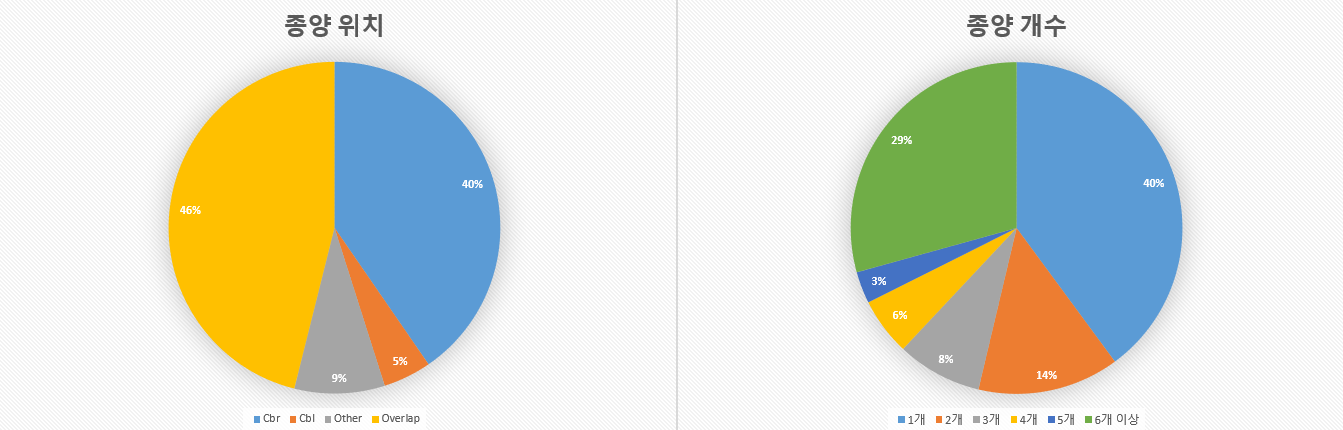

종양위치 케이스 Cbr 404 40.40% Cbl 47 4.70% Other 88 8.80% Overlap 461 46.10% 종양개수 케이스 1개 399 39.90% 2개 138 13.80% 3개 83 8.30% 4개 56 5.60% 5개 31 3.10% 6개 이상 293 29.30% 데이터 분포 그래프